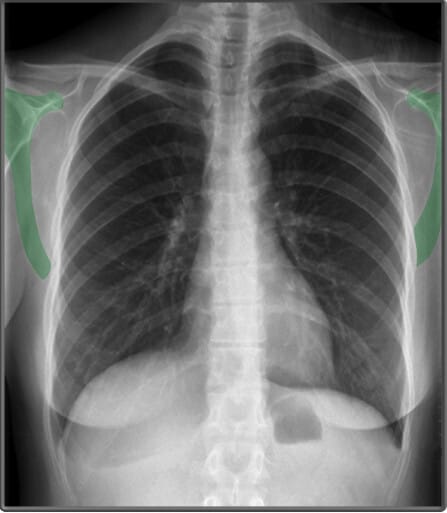

Chest PA view

PA (Posterior-anterior) – 방사선 (X선) 이 후방에서 전방으로 이동

Bones (PA view)

흉부 X-ray에서는 쇄골(clavicle), 흉골(sternum), 견갑골(scapula), 척추(vertebral bodies) 등의 뼈 구조가 보이며, 정상적인 정렬을 확인하는 것이 중요합니다.

| 쇄골 (Clavicle) |

| ✅ 쇄골은 양측 상부에서 가로로 위치하며, 정상적으로 대칭적으로 보여야 합니다. 쇄골의 불균형은 환자의 자세 또는 외상으로 인한 손상을 의미할 수 있습니다. |

| 흉골 (Sternum) |

| ✅ 흉골은 X-ray의 PA(view)에서는 직접 보이지 않고 측면 영상(lateral view)에서 확인할 수 있습니다. 갈비뼈와 연결되어 가슴을 보호하는 역할을 합니다. |

표시한 부분은 복장뼈의 가장 윗부분 두꺼운 뼈인 복장뼈자루 (Manubrium of Sternum)이라고 합니다.| 견갑골 (Scapula) |

| ✅ 어깨뼈라고도 불리며, 흉부 후방에서 삼각형 모양으로 나타납니다. 잘못된 촬영 자세에서는 폐야(lung field)를 가릴 수 있으므로 주의해야 합니다. |

| 척추체 (Vertebral Bodies) |

| ✅ 흉추(Thoracic vertebrae)의 척추체는 X-ray에서 선명하게 보여야 하며, 정상적으로 정렬되어 있어야 합니다. 압박 골절이나 변형이 있는지 평가하는 것이 중요합니다. |